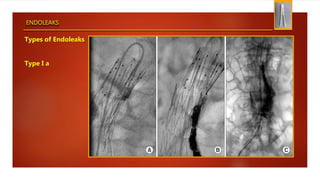

Types of Endoleaks

Type I a

ENDOLEAKS